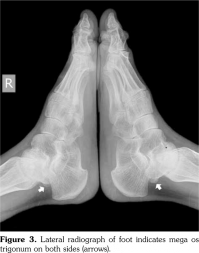

Radiographs of the hands showed enlargement of metaphyses, flattening of epiphyses, and narrowing of joint spaces with no erosions. Lateral radiograph of the foot revealed bilateral large ossified trigonum attached to the talus (mega os trigonum) (Figure 3). Radiographs of the spine showed increased kyphosis, generalized platyspondyly particularly at the thoracolumbar junction, and irregularity of the vertebral end- plates (Figure 4). Magnetic resonance imaging of thoracolumbar spine demonstrated irregularity in vertebral end-plates, multiple disk herniations, and platyspondyly (Figure 5). Dynamic contrast- enhanced magnetic resonance imaging of the wrist did not reveal any signs of synovial inflammation.

Clinical features of PPD have been described in several reports.(9-11) The radiographic features include varying degrees of epiphyseal involvement with enlargement of the epi-metaphyseal region, progressive joint narrowing, generalized platyspondyly, multiple intervertebral herniations, kyphoscoliosis, mega os trigonum and bone destruction with aging.(2,6,10) Our patient had progressive restriction of several joints, IP enlargements, dysplastic bone/cartilage changes, mega os trigonum and platyspondyly, with normal acute phase reactants. The presence of dysmorphic features and the absence of inflammatory signs should alert the physicians for the possible hereditary dysplasias like PPD.